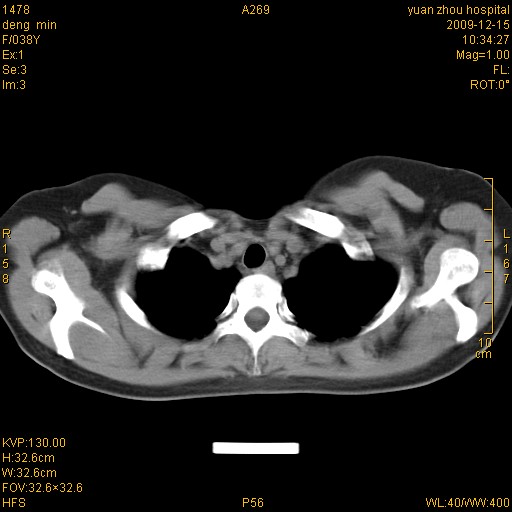

标题: CT23919:F38Y 咳嗽月余 [打印本页]

标题: CT23919:F38Y 咳嗽月余

右肺中下叶、左肺上叶舌段及左肺下叶支气管扩张合并感染。